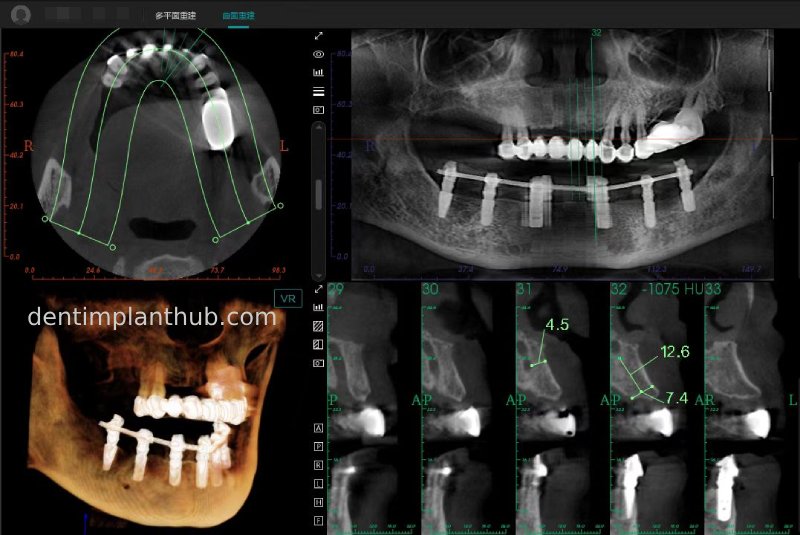

CBCT review results on 13 May '24

46

44

42

32

34

36